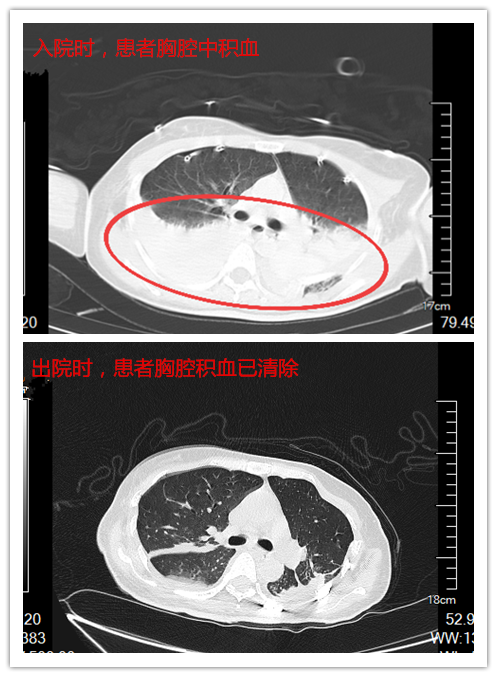

时间就是生命!捷克论坛 立即开通绿色通道,急诊科二部医护人员连夜展开生死营救。侯琨副主任医师紧急召开多学科会诊,在最短时间内确定治疗方案并实施。入院后的凌晨2点,介入三病区接力为患者进行急诊手术,通过造影手术确定体内出血点并紧急止血。术后,回到急诊科二部ICU继续输血治疗。待患者生命体征稳定后,医疗团队于当日先后为她完成了骨盆固定、胸腔镜下止血、血胸清除术和左肺下叶破裂修补术等系列高难度手术。最惊险的是,医生们从患者双侧胸腔引流出血性液体约1200ml,术中清除积血2500ml,相当于5瓶矿泉水的积血,同时术中输血近3000ml,几乎将患者全身血液换了一遍。最终,医护团队凭借精湛技术与默契配合,从死神手中一点点夺回生机。